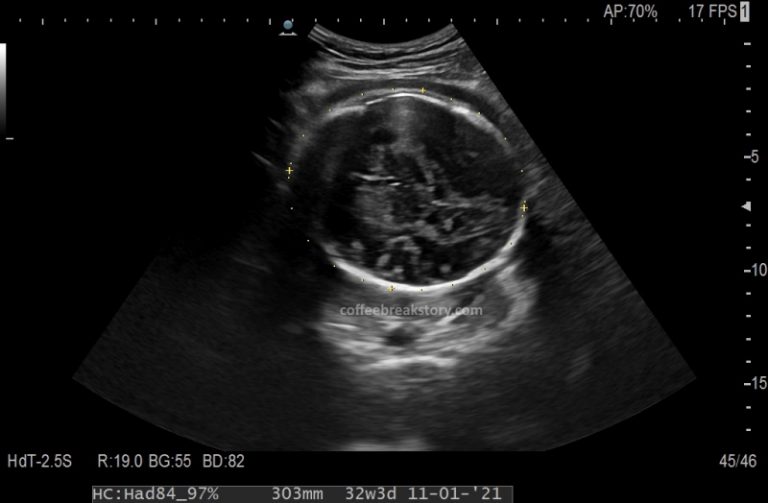

Sebelumnya: Pregnancy Journey: 06 Prenatal Visit (28 Minggu) – Gestational Diabetes Test Hasil USG menunjukkan kalo ukuran badan bayi agak kecil, tapi ukuran kepalanya bagus. Gw ga heran sih, kalo bayinya kecil, orang sampe sekarang aja gw makan masih harus dipaksa-paksa. Gw masih ga ada selera makan, makan / minum kebanyakan dikit langsung ngerasa kembung … Continue reading Pregnancy Journey: 07 Prenatal Visit (32 Minggu) – Menghindari Episiotomi